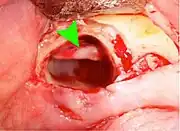

Wisdom teeth removal (extraction) is the most common treatment for impacted wisdom teeth. In the US, 10 million wisdom teeth are removed annually.[20] The procedure can be either simple or surgical, depending on the depth of the impaction and angle of the tooth. Surgical removal is to create an incision in the mucosa of the mouth, remove bone of the mandible or maxilla adjacent the tooth, extract it or possibly section the tooth and extract it in pieces. This can be completed under local anaesthetic, sedation or general anaesthetic.[5] As of 2020, the evidence is insufficient to recommend one type of surgical practice over another.[21]

Coronectomy

Coronectomy is a procedure where the crown of the impacted wisdom tooth is removed, but the roots are intentionally left in place. It is indicated when there is no disease of the dental pulp or infection around the crown of the tooth, and there is a high risk of inferior alveolar nerve injury.[31]

Coronectomy, while lessening the immediate risk to the inferior alveolar nerve function has its own complication rates and can result in repeated surgeries. Between 2.3% and 38.3% of roots loosen during the procedure and need to be removed and up to 4.9% of cases require reoperation due to persistent pain, root exposure or persistent infection. The roots have also been reported to migrate in 13.2% to 85.9% of cases.[31]